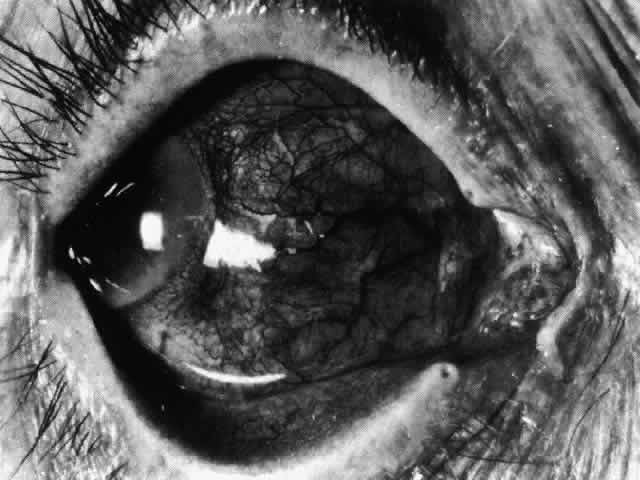

Nodular Anterior Scleritis

Although patients with nodular anterior scleritis resemble those with nodular episcleritis on cursory examination, detailed examination reveals marked differences. The nodule or nodules (they may be multiple) consist of scleral tissue that is immovable episclera is tightly adherent to the nodule, which is tender to the touch. Although the sclera sometimes becomes transparent below the nodule, it does not become necrotic, nor does the condition extend beyond the site of the nodule, as occurs in necrotizing scleral disease (Fig. 36).

(see Fig. 28; Figs. 34 and 35). The edematous

Fig. 34. Scleral edema has displaced all the vessel layers forward. Area surrounding the nodule is acutely inflamed.

Fig. 35. Multiple scleral nodules. Surrounding inflammation is deep and intense. (Watson PG: Management of scleritis. In: Recent Advances in Ophthalmology, Vol 5. London, Churchill-Livingstone, 1975)